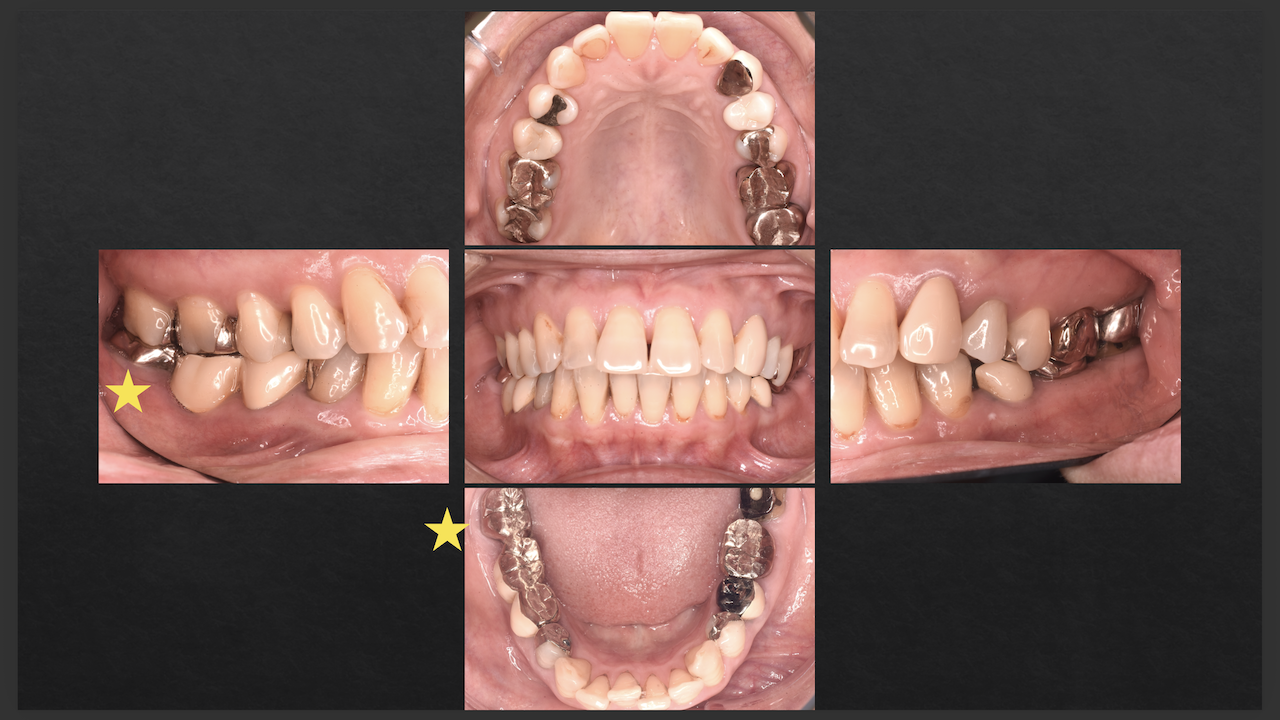

次は東京から参加のN先生。

術前/術後を比較した。

#29

#4

ラバーダム防湿をして行った根管治療の威力がわかったと思う。

素晴らしいケースだ。